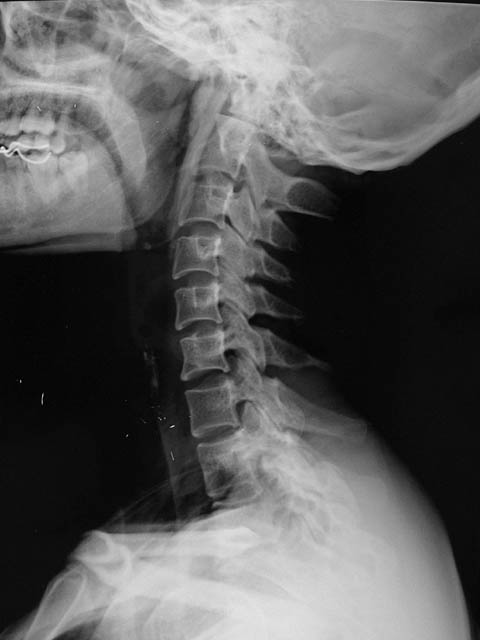

女,35岁,颈部不适一周.

考虑颅底凹陷症。以前缘型可能性大。

平片上看环椎与颅底有融合,提示颅底凹陷,必要时因mri检查,看是单纯的凹陷还是chiari畸形。

应该是环枢关节半脱位伴颅底凹陷。

但是不一定就是chiari畸形,因为环枢半脱位和颅底融合凹陷还见于其他病,比如类风湿关节炎。所以要做个mri。

补充两句,诊断寰枢椎不稳(性质待查),寰枕融合。须查动力x线片还有mri。另外我看咽后壁好像肿胀明显,当然我是外行,大家指导。

寰枕融合、颅底凹陷、寰枢关节半脱位。

我查过书了支持sdqzwyx:寰枕融合、颅底凹陷、寰枢关节半脱位。理由1、枕大孔前后缘连线,齿状突尖端超过连线的上方即为颅底凹陷。2、寰枕间应有寰枕关节,此图未见。3、枢椎齿状突两侧不对称。请老师点评。

齿状突上端在chamberlain线以上3mm为异常。